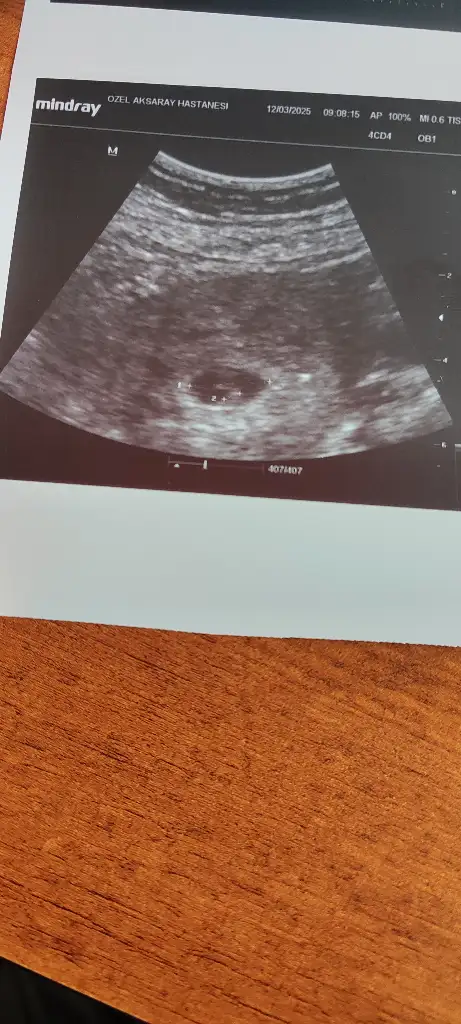

6 haftalik karından ultrasyon tahminde bulunabilir misiniz

Merhaba. SAT’a göre 7+5. Abdominal ultrason.